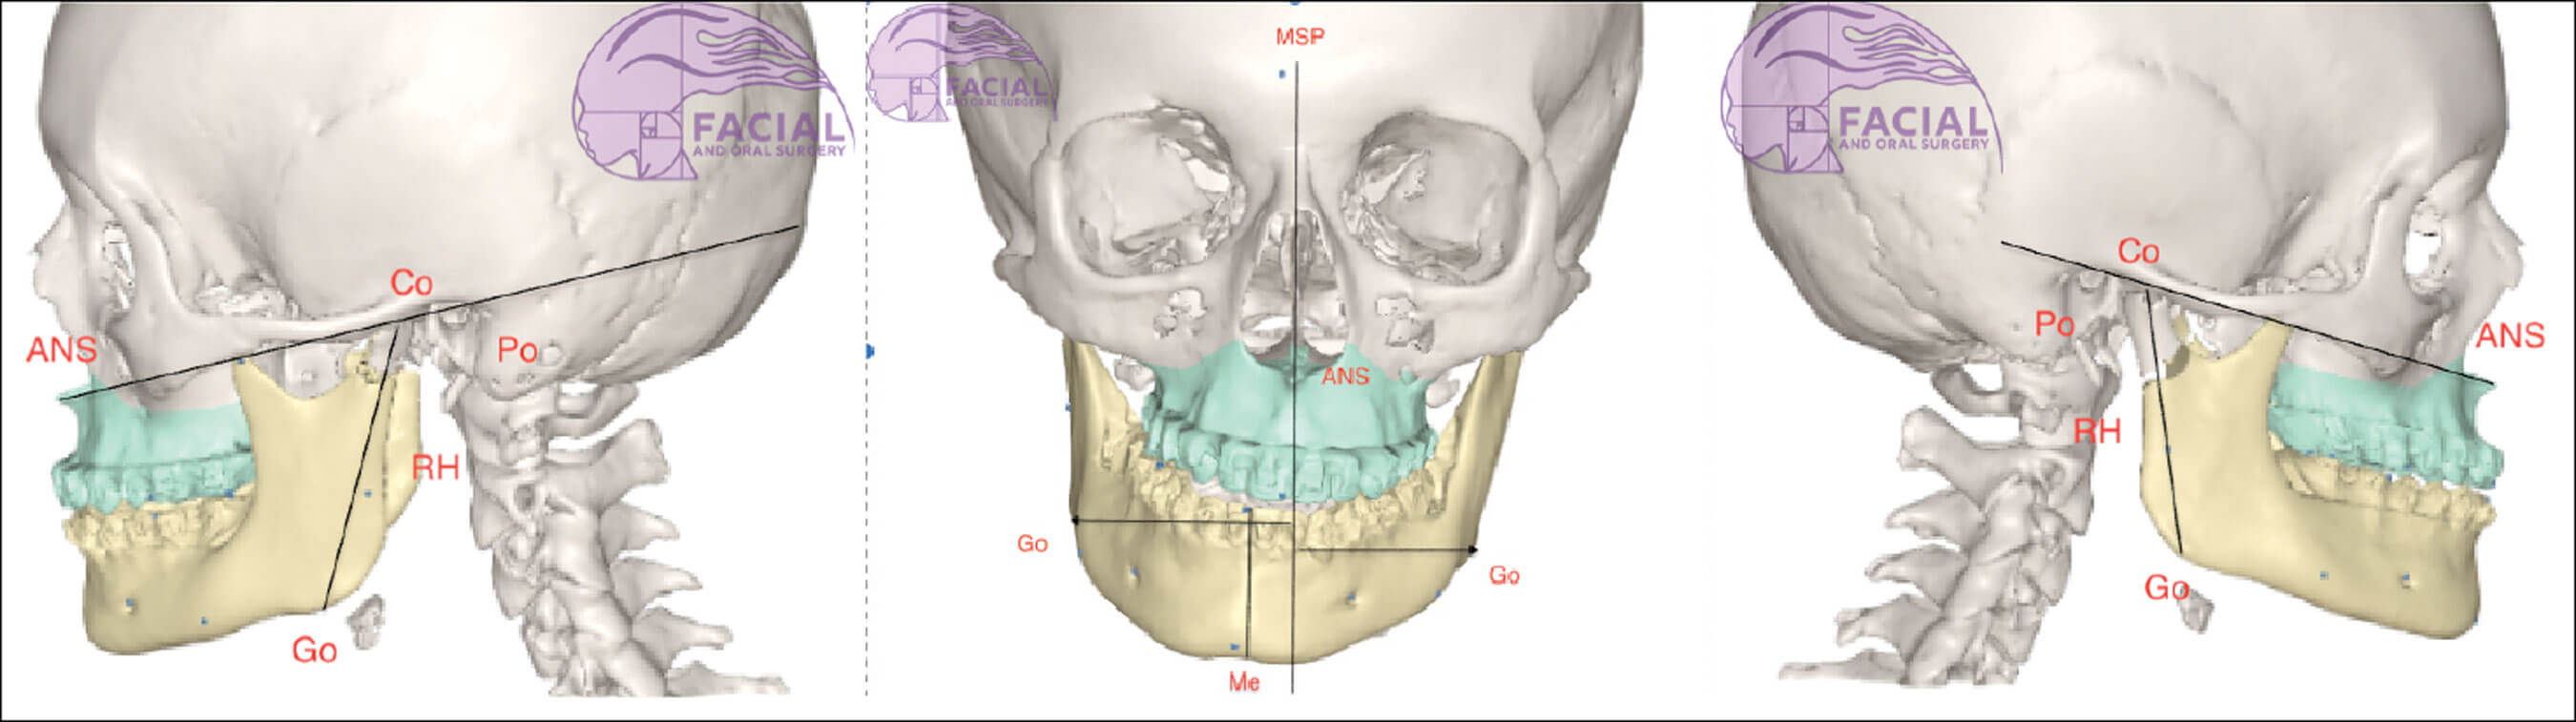

Figure 1: Mid-sagittal plane: Line through nasion, anterior nasal spine and menton. Menton: Most inferior part of the bony chin in the median plane. Gonion: Most posteroinferior point at the angle of mandible. Co: Most superior point of condylar head. Ramus height: Co to gonion.

- Diagnosis: Skeletal base III growth discrepancy, due to maxillary hypoplasia complicated by left hemi-mandibular elongation causing mandibular asymmetry to the right. Yaw dominant mandibular asymmetry (see Figure 1, 2a and 3).

- Treatment: Combined treatment involving pre-surgical orthodontic treatment followed by surgery (bimaxillary osteotomy - Le Fort 1 advancement and asymmetric mandibular rotation to correct asymmetry) and post-surgical orthodontic treatment (see Figure 1, 2a, 3).